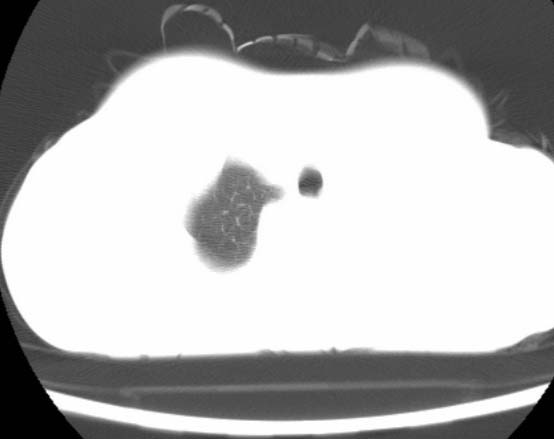

标题: CT25648:求教:是肺发育不全还是结核?

女  20岁。一月前咳血,诊“肺结核”抗痨治疗一月后,咳血停止,现复查。病人精神好。前后ct片对比未见明显变化。既往体检“正常”

1)考虑左肺结核并肺不张、支气管扩张。2)纵隔疝。

考虑左肺结核,左肺毁损,纵膈左偏,既往体检正常不可靠,tb一个月也不会这个样子的,有钙化,应该病程较长,冰冻三尺非一日之寒!

左肺发育不全。